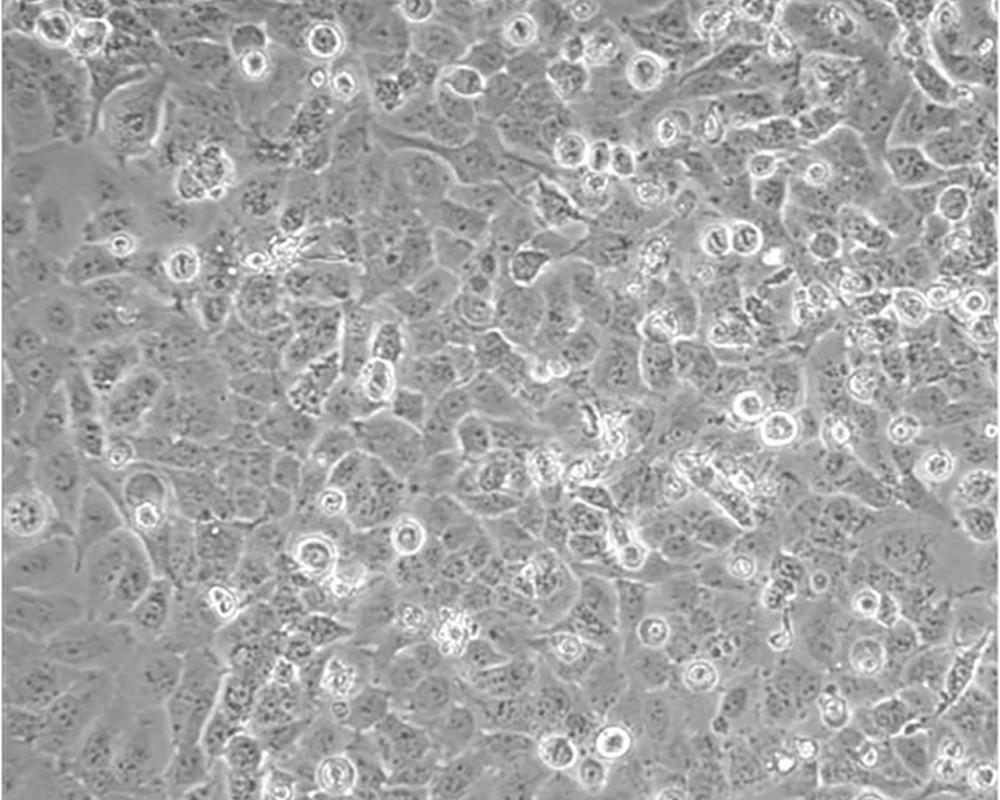

NCI-H23

產品名稱 NCI-H23

組織來源 肺腺癌;男性

細胞種屬 Homo sapiens, human

生長特性 Homo sapiens, human

培養基 RPMI-1640+10% FBS+1% P/S

形態特征 epithelial

細胞描述 該細胞源于一位51歲患有非小細胞肺癌黑人男性患者的治療前的腫瘤組織,表達C-myc、L-myc、v-src、v-abl、v-erb B、c-raf 1、Ha-ras、Ki-ras、N-ras RNAs;該細胞攜帶K-ras 12突變;p53基因246位密碼子突變ATC→ATG;表達PDGF A和B鏈的異源mRNA;表達TGFα、TGFβ和EGFR;角蛋白 5、8和18陽性,波形蛋白陽性,神經絲蛋白陰性,左旋多巴脫氫酶陰性;據報道,在軟瓊脂中該細胞形成克隆的效率為9.7%。